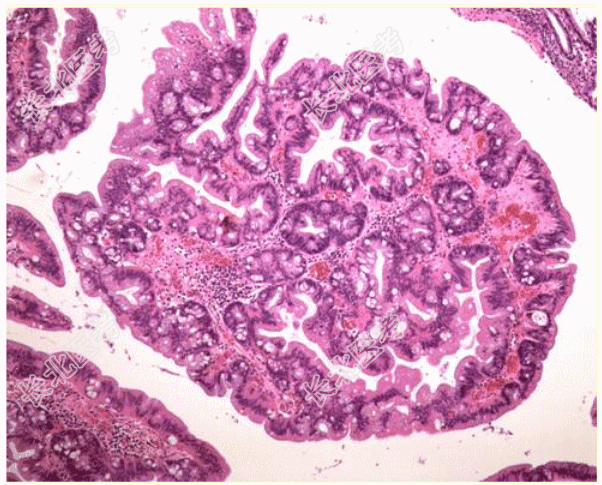

- [材料题] 患者男,79岁,肠镜发现1.2 cm×1.2 cm乙状结肠息肉,镜下图像如图所示。病理诊断为传统锯齿状腺瘤。